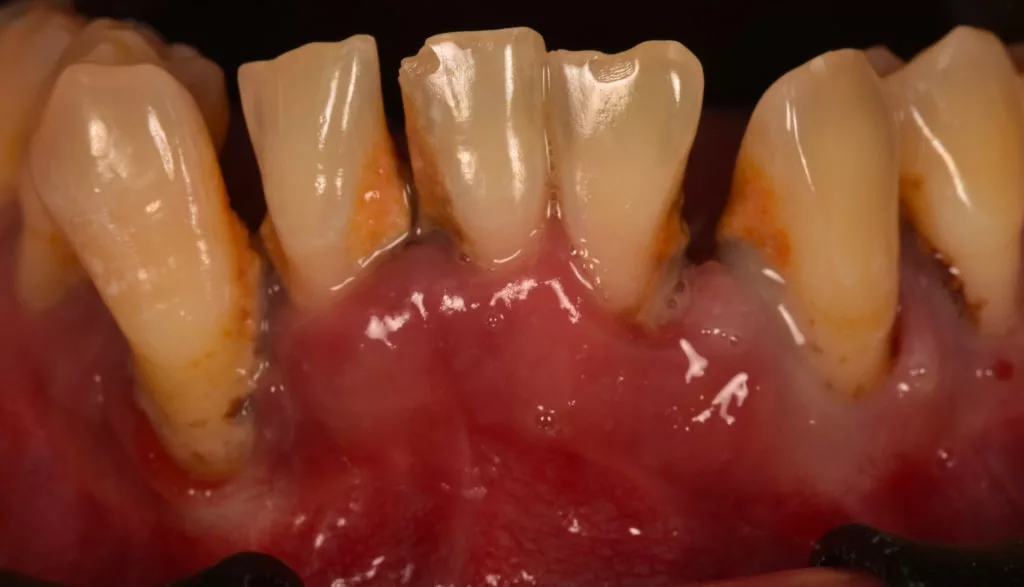

La parodontite, quant à elle, implique une destruction de l’os alvéolaire et donc une diminution du support de la dent pouvant aller jusqu’à la perte de la dent. Des mobilités peuvent apparaître, entrainant des changements dans l’alignement des dents. Du tartre est présent sur et sous les gencives.